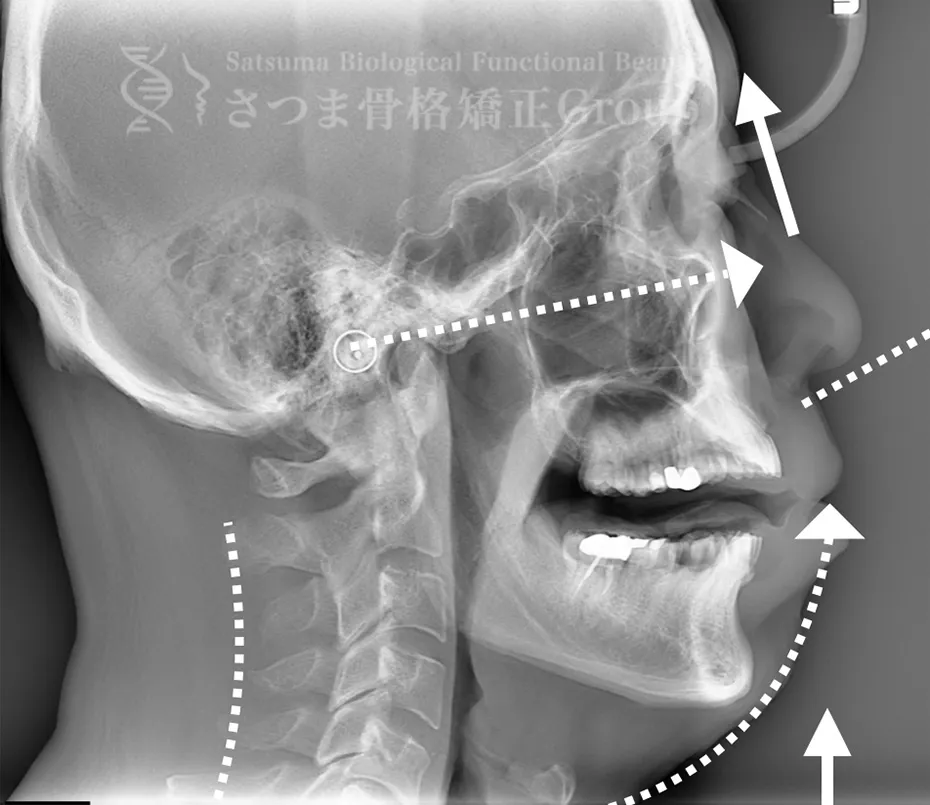

AFTER(マウスピース使用時)

整骨後、形成したマウスピースで形と顎関節の前方回転を誘導。上部頸椎のリリースを促進し、自家矯正力が働きやすいように誘導。蝶形骨口蓋縫合と蝶形骨上顎縫合をモビライゼーションし、可動をブーストし中顔面を短縮。

After the osteopathy, the custom-formed mouthpiece guides the shape and promotes forward rotation of the temporomandibular joint.

It facilitates the release of the upper cervical spine and encourages the body’s natural self-correcting ability.

Mobilization of the sphenopalatine suture and the sphenomaxillary suture boosts mobility and shortens the midface.

口蓋骨の下方変位 下顎位の滑落 ストレートネック 中顔面と人中が伸びて見える

Inferior displacement of the palatine bone Sagging of the mandibular position Straight neck The midface and philtrum appear elongated

AFTER

口蓋骨を上方に整復 下顎位が上がる ストレートネックの改善 中顔面と人中が短縮し小顔に見える

Repositioning the palatine bone upward The mandibular position is elevated Improvement of straight neck The midface and philtrum are shortened, giving the appearance of a smaller face